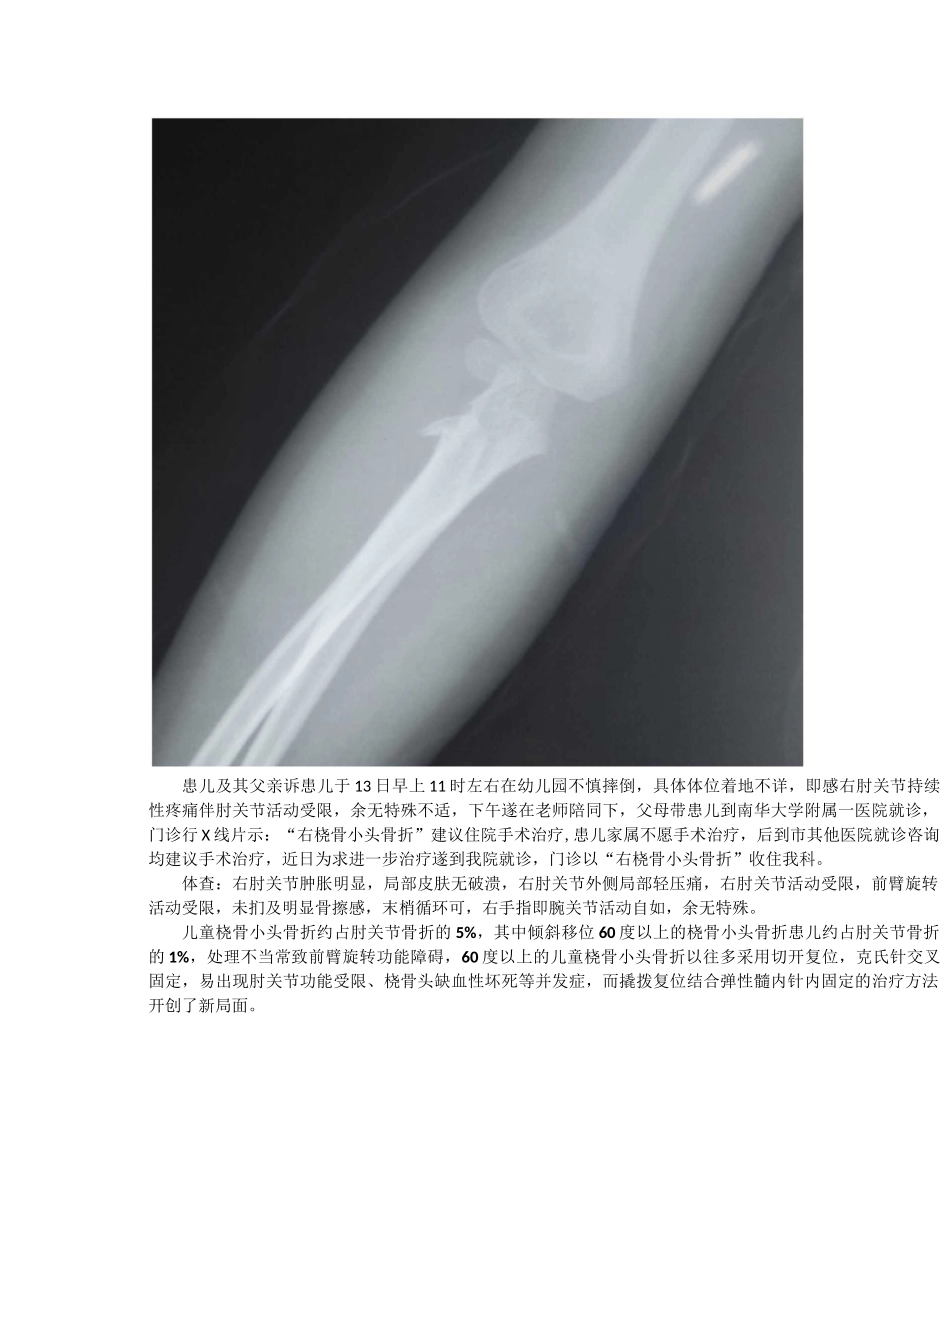

>90%小儿桡骨小头骨折经皮克氏针辅助撬拨复位弹性髓内钉内固定Qc\移位成角3J2.A 橈骨颈骨折分度。依据骨折的移位和成角分度通常来讲成交小于 30 度桡骨颈骨折只需长臂石膏或夹板固定 2-3 周。角度大于 30 度和(或)移位大于 5MM 的桡骨颈骨折,一定要进行骨折复位。患儿杨欣蕾,女,5 岁,因摔伤致右肘关节肿痛办活动受限 1 天于 2018 年 6 月 14 日收住我科。入院 X 线片示:患儿及其父亲诉患儿于 13 日早上 11 时左右在幼儿园不慎摔倒,具体体位着地不详,即感右肘关节持续性疼痛伴肘关节活动受限,余无特殊不适,下午遂在老师陪同下,父母带患儿到南华大学附属一医院就诊,门诊行 X 线片示:“右桡骨小头骨折”建议住院手术治疗,患儿家属不愿手术治疗,后到市其他医院就诊咨询均建议手术治疗,近日为求进一步治疗遂到我院就诊,门诊以“右桡骨小头骨折”收住我科。体查:右肘关节肿胀明显,局部皮肤无破溃,右肘关节外侧局部轻压痛,右肘关节活动受限,前臂旋转活动受限,未扪及明显骨擦感,末梢循环可,右手指即腕关节活动自如,余无特殊。儿童桡骨小头骨折约占肘关节骨折的 5%,其中倾斜移位 60 度以上的桡骨小头骨折患儿约占肘关节骨折的 1%,处理不当常致前臂旋转功能障碍,60 度以上的儿童桡骨小头骨折以往多采用切开复位,克氏针交叉固定,易出现肘关节功能受限、桡骨头缺血性坏死等并发症,而撬拨复位结合弹性髓内针内固定的治疗方法开创了新局面。术中操作:HenqyangTCMORTHospitalQCr201B.06.15,1^7:41IDt20100^15165741HenqyangTCMORTHospitalSiemens术后复位满意,内固定正常:术后外观:术后常规前臂旋后位石膏托外固定。